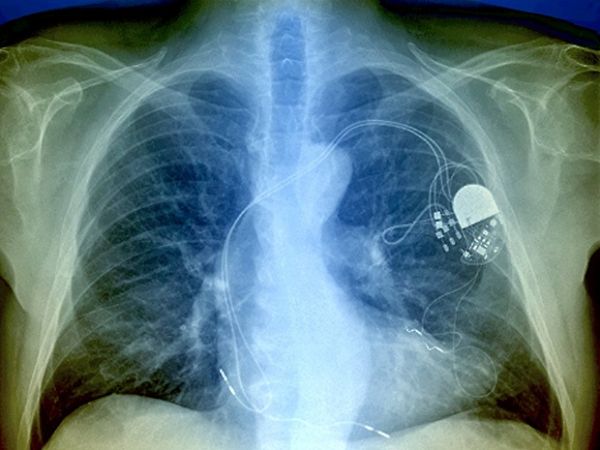

O marca-passo é um dispositivo pequeno e leve que fornece estimulação elétrica, que é feito por um gerador de pulsos e eletrodos, ao coração. Esse gerador elétrico é constituído por um circuito eletrônico miniaturizado e também com uma bateria compacta. Esse equipamento é muito importante para algumas pessoas que têm problemas no coração.

Marca-passo câmara única: nesse dispositivo o eletrodo é instalado no ventrículo direito do paciente, ou seja, na parte inferior do coração.

Marca-passo câmara dupla: já nesse caso são colocados dois eletrodos, um que fica no átrio e outro que se instala no ventrículo direito.

Nessa situação, existem dois tipos mais comum de cirurgia, sendo a endocárdica, que é a introdução dos eletrodos do marca-passo por meio de veias que chegam até o coração e também tem a cirurgia epicárdica. Nesse segundo método é mais comum ser feito com crianças, pois é realizado sob anestesia geral, e os eletrodos são colocados diretamente no músculo cardíaco e o marca-passo em uma bolsa criada bem abaixo da pele no abdome.